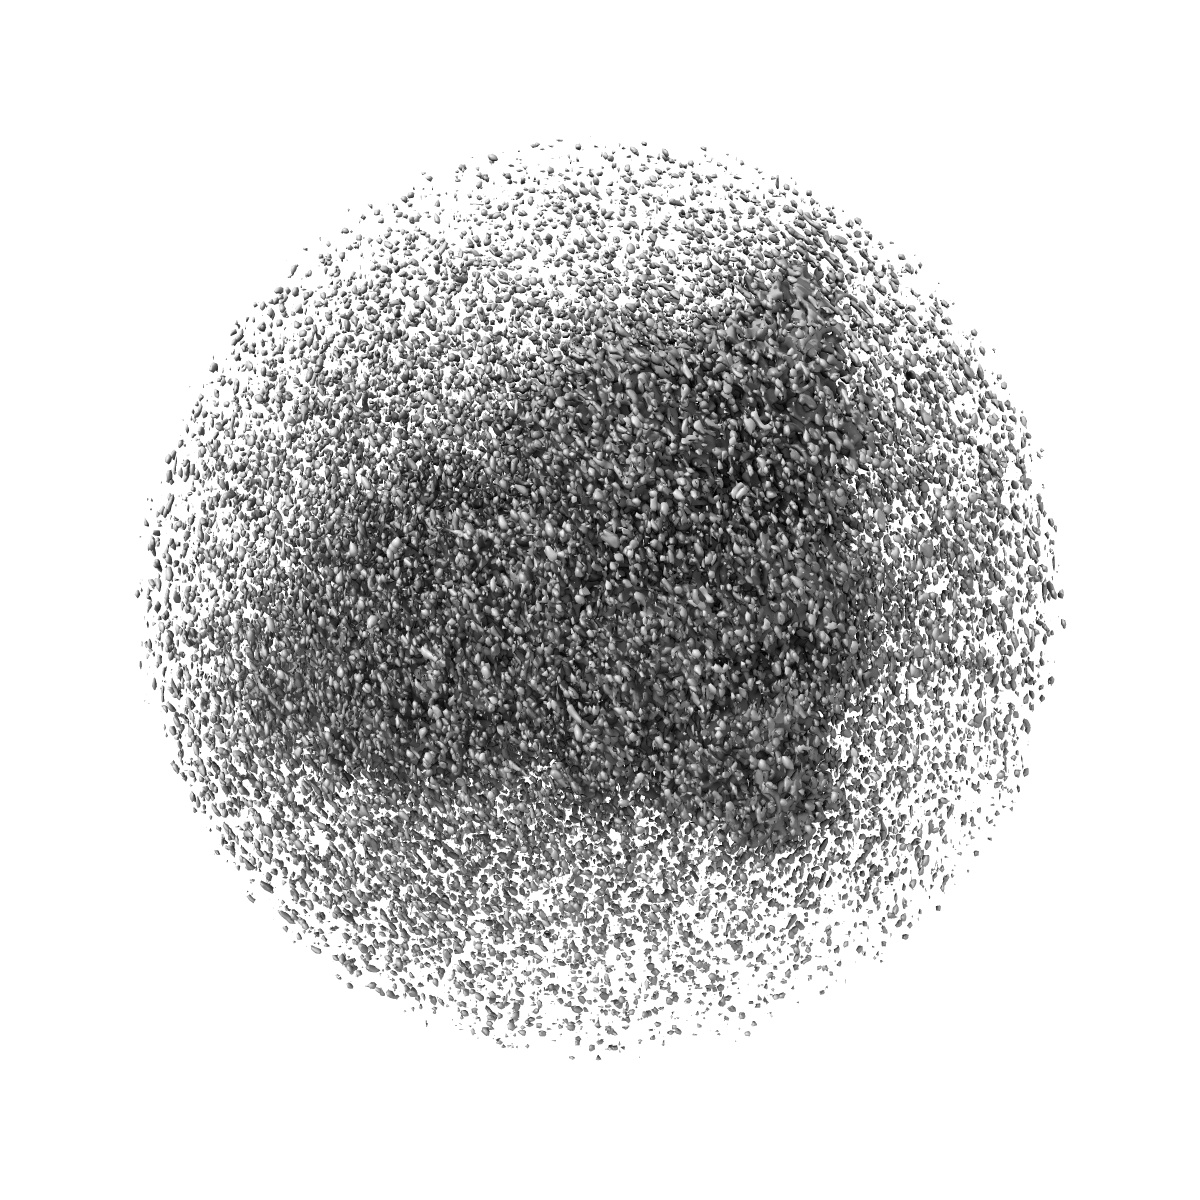

Structure of the SARS-CoV-2 spike glycoprotein in complex with a human single domain antibody n3113 (UDD-state, state 1)

Single-particle3.7 Å

Sample: Complex of SARS-CoV-2 spike with n3113